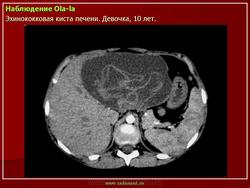

Приводим клиническое наблюдение. Больная Г- ва В.А. 35лет , жалоб не предьявляет. При профилактическом осмотре на УЗИ выявлено: по органам без особенностей, тоны сердца приглушены, пульс 79 ударов в минуту, А/Д 140/95мм.рт.ст. Живот мягкий, безболезненный. Лабораторные данные – общий анализ крови - эозинофилия, общий анализ мочи, коагулограмма в пределах возрастной нормы. При УЗИ органов брюшной полости выявлено два кистозных образования, занимающие правую долю с характерной для Э многослойной капсулой (рис 7а). КТ, МРТ уточнили кистозный характер изменений, их локализацию, наличие толстой капсулы (рис 7б). На основании комплексного анализа поставлен диагноз Э кисты.

Рис 7. Э печени а)УЗИ – кистозное образование с многослойной капсулой, эхогенной взвесью, краевым ослаблением УЗ б, в) РКТ, МРТ – кистозные образования, толстая капсула